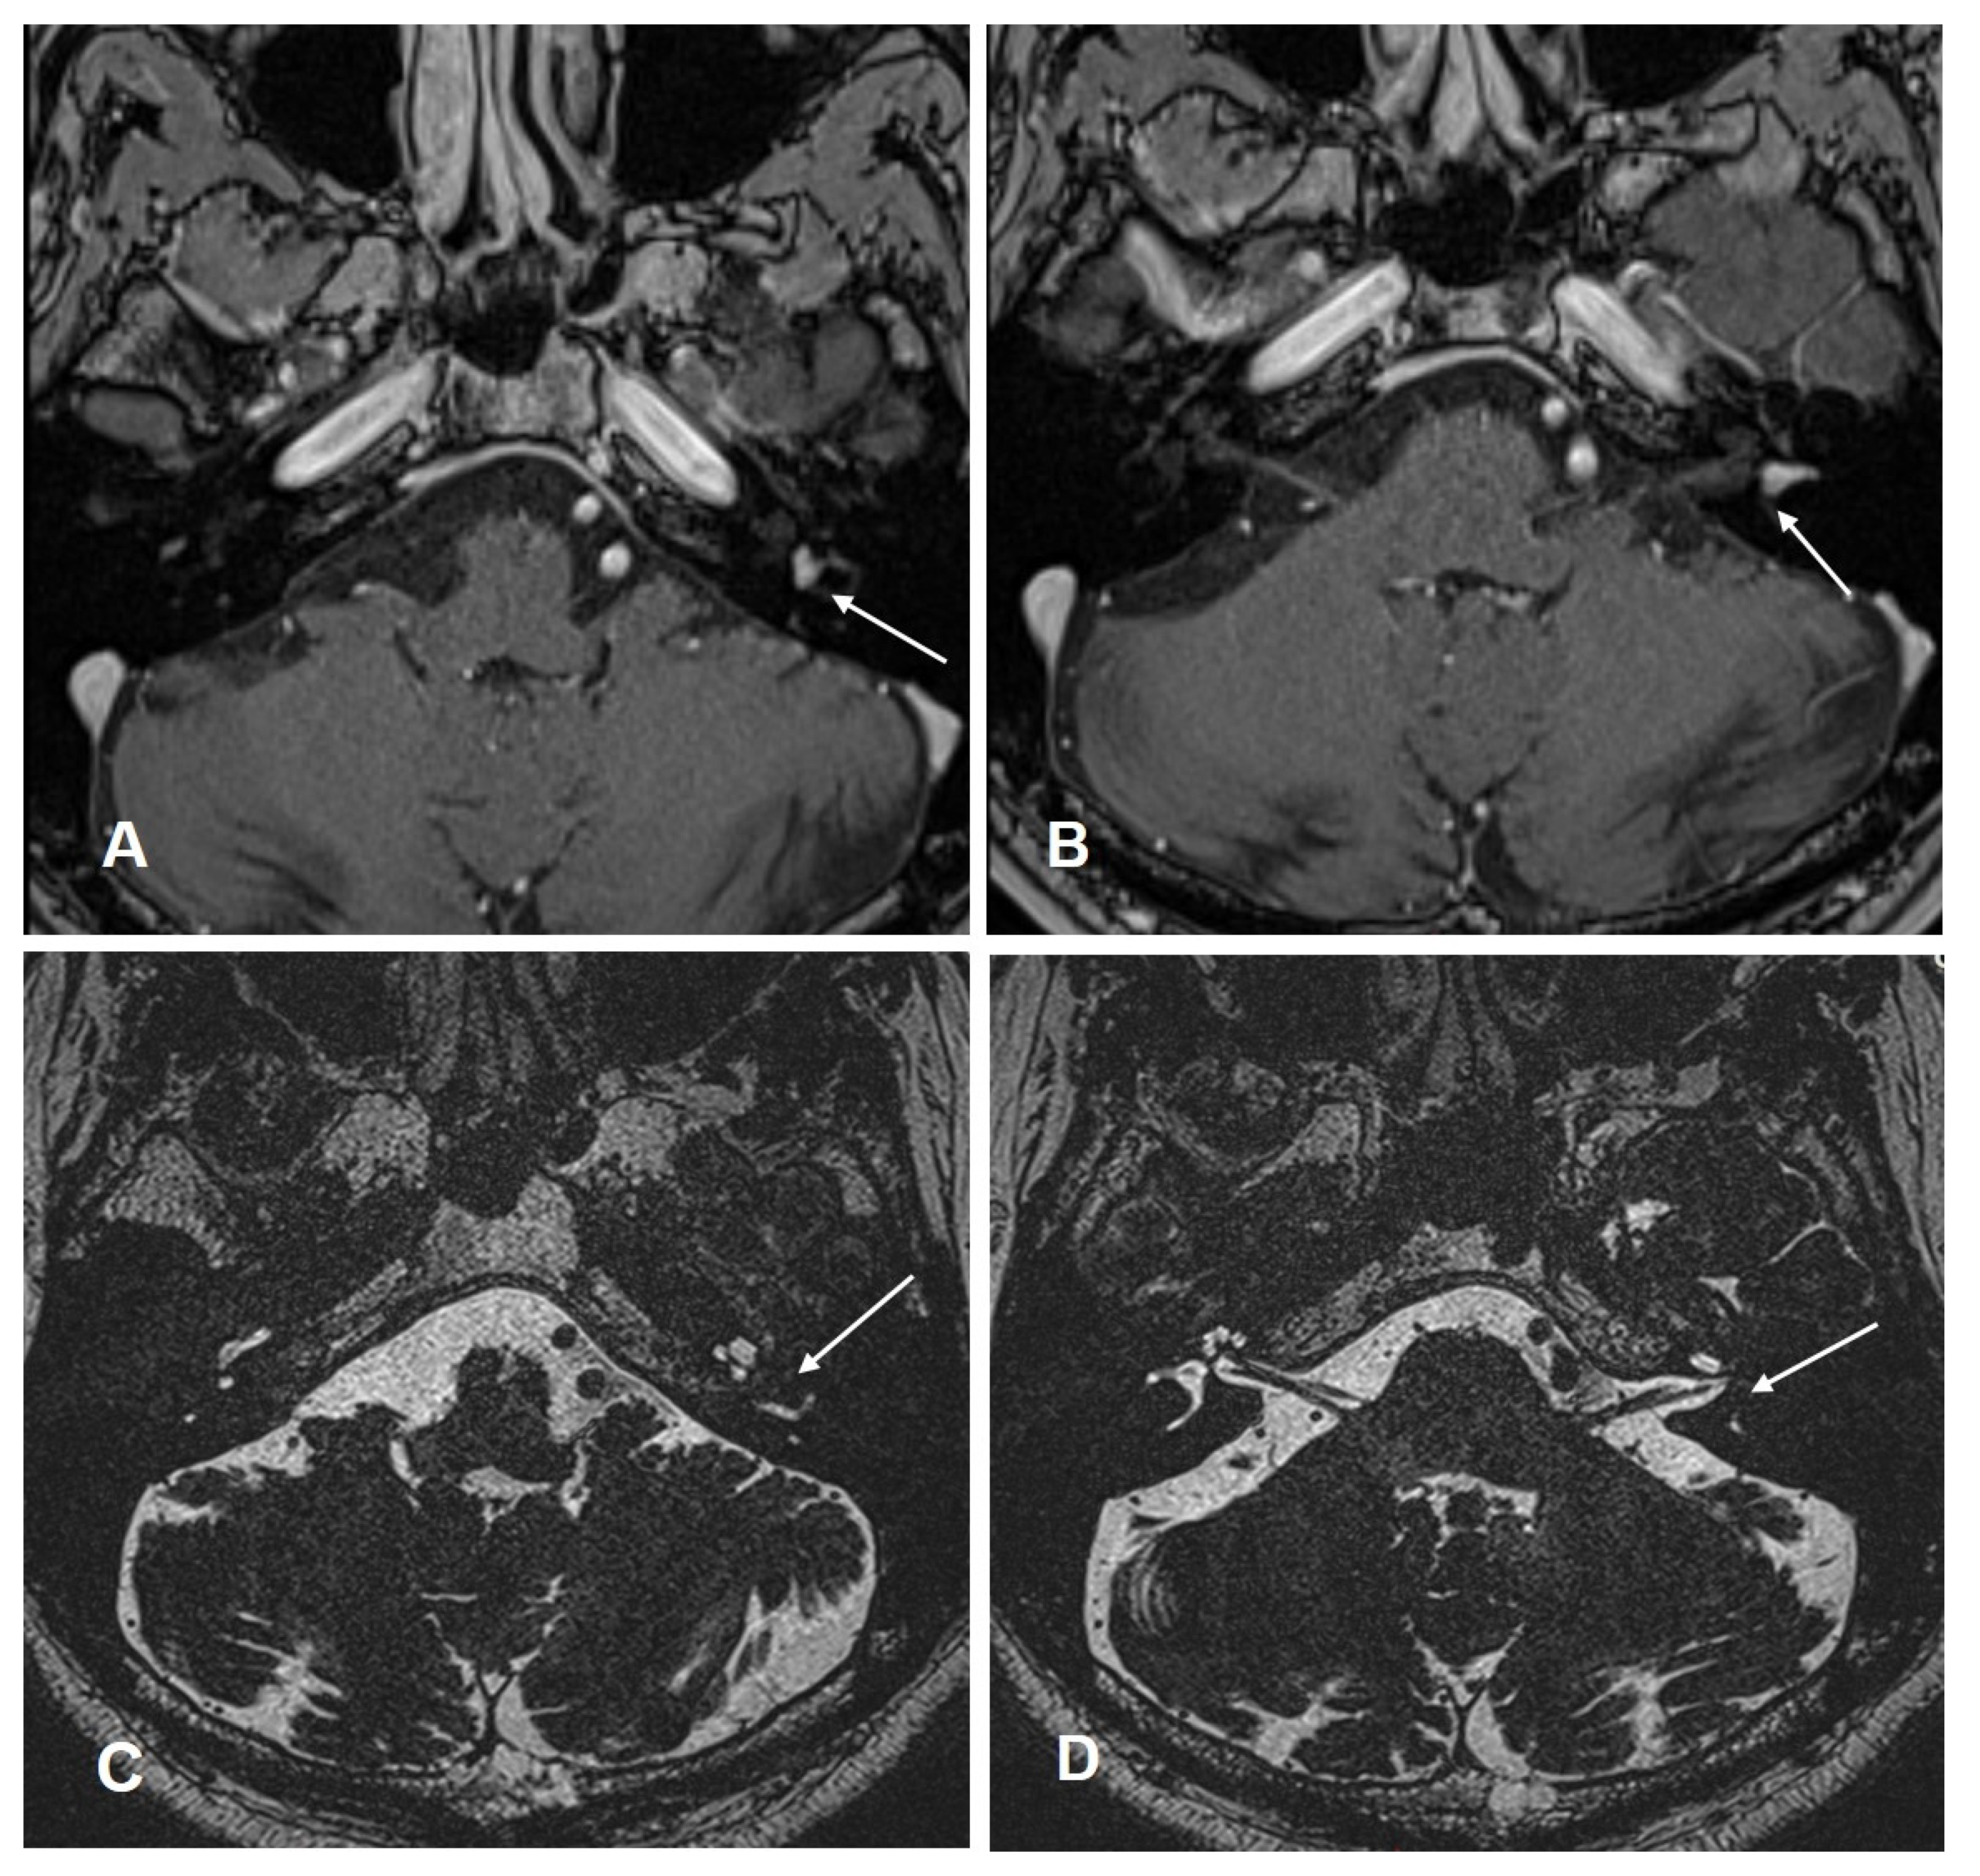

Patient #6 had intravestibular ILS (in the anterior part of the horizontal semicircular canal, Figure 5A–D). Therefore, it was necessary to use a translabyrinthine approach during tumor removal. For implantation, the round window approach was used. After surgery, the patient developed a transient facial nerve paralysis (House–Brackmann score IV) treated with intravenous prednisone, as per local SOP (dosage during surgery 250 mg; after surgery-tapering scheme down to 5 mg a day) and targeted physiotherapy. Four months after surgery, the facial nerve function was restored.

Figure 5. Case #6: cMRI images demonstrating the intravestibular schwannoma. (A,B): T1 weighted VIBE 3D with fat saturation prepulses after the intravenous administration of gadolinium. White arrow: intravestibular schwannoma in the ampulla and in the anterior part of the horizontal semicircular canal. (C,D): T2 weighted SPACE sequences. (C) Intravestibular schwannoma in the anterior part of the horizontal semicircular canal (white arrow). (D) ILS in the ampulla (white arrow).